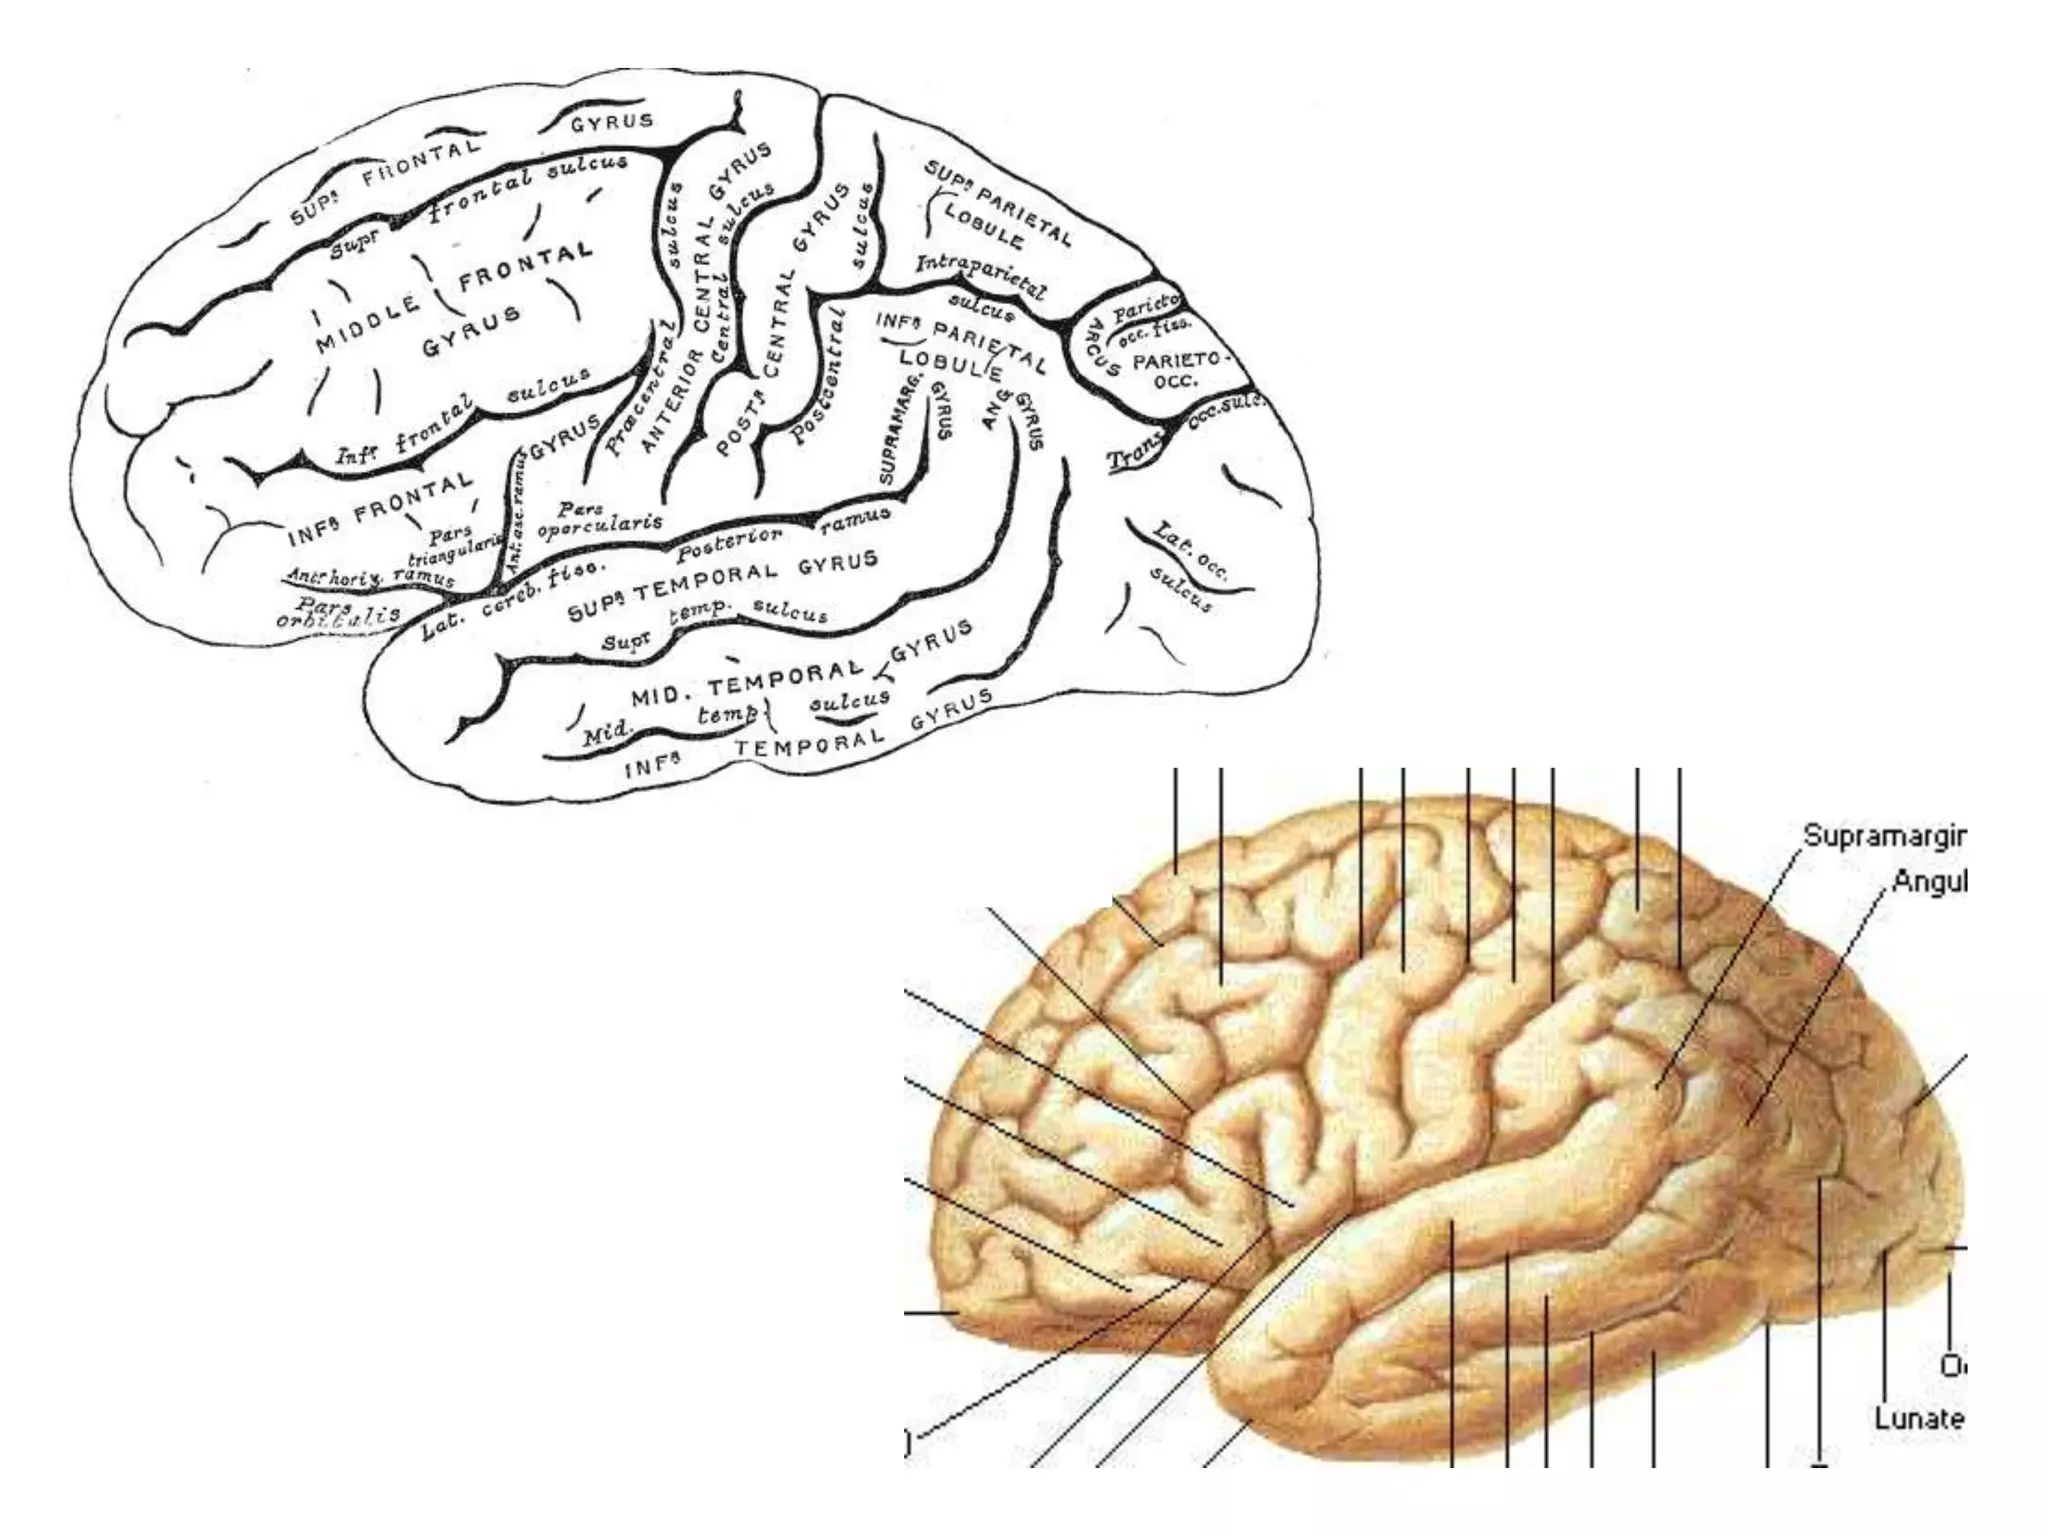

CEREBRAL HEMISPHERES

• 4 lobes are present in each hemisphere. They are

demarcated by fissures.

• Each lobe is again divided into gyri by sulci . They are

named accordingly.

FISSURES

1. Central sulcus

2. Sylvian fissure

3. Calcarine sulcus (temporo-occipital fissure)

4. Parieto-occipital fissure :

Seen medially. Better seen on midline saggital MRI.

FRONTAL LOBE

Anterior to central sulcus and supr. to sylvian fissure.

1. Precentral gyrus

2. Lateral surface – supr. frontal gyrus

middle frontal gyrus

infr. frontal gyrus

PARIETAL LOBE

• Parieto-occipital differentiation.

• Parieto-temporal differentiation ??

1. Post central gyrus

2. Superior parietal lobule

3. Inferior parietal lobule

TEMPORAL LOBE

Sylvian fissure and calcarine sulcus - borders

1. Superior temporal gyrus -

Heschl gyrus – floor of sylvian fissure & above supr.

temporal gyrus. It is found on ‘flat top’ surface of supr.

temporal gyrus.

2. Middle temporal gyrus

3. Inferior temporal gyrus